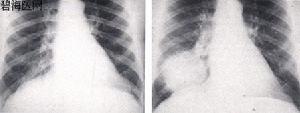

(一)中央型肺癌

多為一側肺門類圓形陰影,邊緣多多毛糙,有始有分葉表現;或為單側性不規則的肺門部腫塊,癌與專一性肺門或縱隔淋巴結融合而成的表現;也可以肺不張或阻塞性肺炎並存,形成所謂“S”型的典型肺癌的X線徵象。肺不張、阻塞性肺炎、預先性肺氣腫皆由於癌對氣管完全阻塞或部分阻塞引起的間接徵象。在體層攝片、支氣管造影可見到支氣管部分不規則增厚、狹窄、中斷或腔內腫物;視支氣管阻塞的不同程度可見有師尾狀、杯口狀況或者截平狀中斷。腫瘤發展至晚期侵犯鄰近器官和轉移淋巴結腫大,可見得有關肺門淋巴結腫大、縱隔塊狀影和氣管向健側移位;隆凸下淋巴結腫大可引起左右支氣管的壓跡、氣管分叉的高度變鈍和增寬以及食管中段局部受壓等;壓迫膈神經引起膈麻痹,可出現膈高位和矛盾運動;侵犯心包時,可引起心包積液等晚期徵象。

(二)周圍型肺癌

常呈預先性小斑片狀陰影,邊緣不清,密度較淡,易誤診為炎症或結核。如動態觀察腫塊增大呈圓形或類圓形時,密度增高,邊緣清楚常呈分葉狀,有切跡或毛刺,尤其是細毛刺或長短不等的毛刺。如癌向肺門淋巴結蔓延,可見其間的引流淋巴乾增粗呈套索狀,伊可引起肺門淋巴結腫大。如發生癌性空洞,其特點為口動壁較厚,多偏心,內壁不規則,凹凸不平,也可伴有液平面。易侵犯胸膜,引起胸腔積液,也易侵犯肋骨,引起骨質破壞。